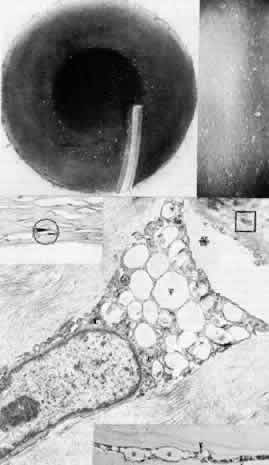

Among the classic corneal dystrophies, macular dystrophy, unlike granular and lattice dystrophies, is an autosomal recessive disorder and is far less common. It usually begins in the first decade of life and leads to progressive visual deterioration as the stroma becomes generally cloudy, with superimposed dense, gray-white spots (Figs. 5 AND 11; Color Plate 1H). Unlike granular dystrophy, these macular spots have indefinite edges and the intervening stroma is not clear. Young patients exhibit axial lesions in the superficial layers of the cornea, but with time, lesions approach the periphery and extend throughout the entire stromal thickness. Corneal thinning confirmed by central pachymetry has been documented.129 Also unique is primary involvement of the endothelium as evidenced clinically by the presence of guttate changes of Descemet's membrane.

Fig. 11. Macular corneal dystrophy. Top left. Clinical appearance of cornea features diffuse haze extending to the limbus with superimposed, dense gray-white spots. Bottom left. Light photomicrograph of posterior cornea shows endothelial cells staining intensely positive for acid mucopolysaccharide. Guttate excrescences (*) of Descemet's membrane (DM) are frequent. The stroma also shows positive staining for acid mucopolysaccharide both diffusely extracellularly and intensely within keratocytes (circled) (colloidal iron × 500). Right. Transmission electron micrograph discloses typical fibrillary granular deposits within keratocytes (K), throughout the posterior layer of Descemet's membrane, and within the endothelial cells (En). The anterior banded region of Descemet's membrane (bracketed) is not affected (× 3500).

The lesions in macular corneal dystrophy stain intensely with alcian blue and colloidal iron, minimally with PAS, and not at all with Masson's trichrome. Birefringence is decreased. The lesions have been histochemically identified as an abnormal keratan sulfate-like glycosaminoglycan that accumulates extracellularly within the stroma and Descemet's membrane and intracellularly within keratocytes and endothelium.130

As would be typical of an autosomal recessively inherited condition, macular dystrophy presumably results from deficiency of a hydrolytic enzymes (sulfotransferase) and may thus be considered a localized mucopolysaccharidosis.131 The effect of altered glycosaminoglycan metabolism is evident at the cellular level; on transmission electron microscopy, keratocytes and endothelial cells exhibit distention of rough-surfaced endoplasmic reticulum cisternae. With the acridine orange technique, compensatory generalized hyperactivity of the lysosomal enzyme system has been demonstrated.132 Eventually the accumulated undigested storage products engorge the cells, and the cells ultimately degenerate or rupture. The derivation of these intracytoplasmic storage vacuoles from endoplasmic reticulum suggests that the biochemical lesion in macular dystrophy occurs at a different metabolic location than in the systemic mucopolysaccharidoses, since in the latter, storage products accumulate within lysosomelike intracytoplasmic vacuoles associated with the Golgi complex.133 Snip and associates134 were able to determine that the storage phenomenon affecting endothelium and Descemet's membrane is likely also primary, since the intracellular and extracellular lesions appear ultrastructurally comparable to those evident in the keratocytes and stroma.

Two subtypes of macular dystrophy have been immunohistochemically identified. Type I is most prevalent and is characterized by the absence of antigenic keratan sulfate in the cornea as well as in the serum; it, in fact, may represent a more widespread systemic disorder of keratan sulfate metabolism.135 In type 2, antigenic keratan sulfate is present in both cornea and serum.

The treatment for macular dystrophy is corneal transplantation. Recurrence in the graft has been reported.119,136